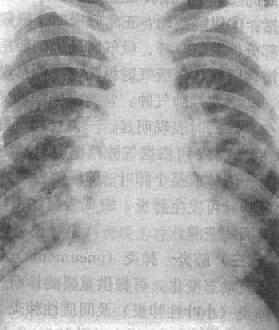

粟粒型肺结核病灶小,透视常难以辩认,故拟诊急性粟型肺结核时应摄片检查。病变早期整个肺野可呈毛玻璃样密度增高。约10日后可出现均匀分布的1.5~2mm大小、密度相同的粟粒状病灶,正常肺纹理常不能显示(图3-1-22)。经过适当治疗后。病灶可在数月内逐渐吸收,偶尔以纤维硬结或钙化而愈合。病变恶化时,可以发生病灶融合,表现为病灶增大,边缘模糊,甚至形成小片状或大片状影,并可干酪样化而形成空洞。

图3-1-22 急性粟粒型肺结核

两肺野布满粟粒状病灶,分布均匀,肺门大

(2)亚急性或慢性血行播散型肺结核:系少量结核杆菌在较长时间内多次进入血流播散至肺部所致。患者抵抗力较强,症灶多以增殖为主,临床症状可不明显或有反复的发热、畏寒或轻度结核中毒症状如低热、盗汗、无力、消瘦等。